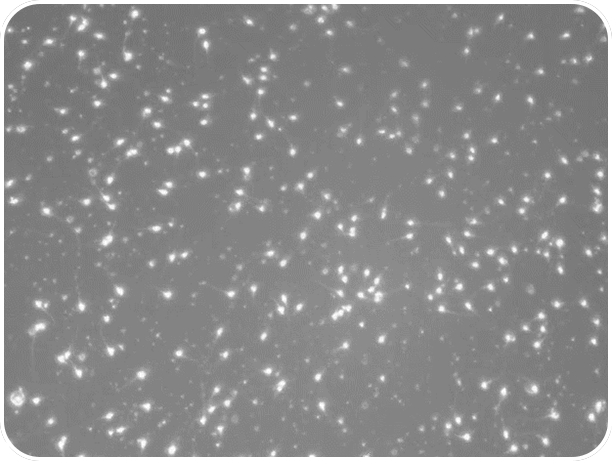

精子数量肉眼可见的减少,减少的速度甚至也是越来越快(图:Hagai et al.)